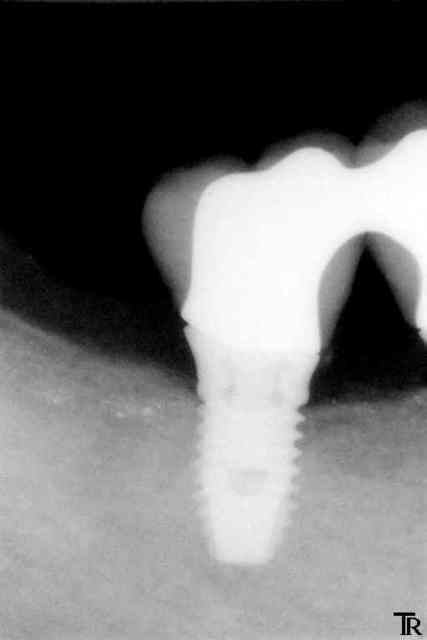

Allez un cas un petit peu limite

pilier Ti procera à fond et couronnes avec un léger défaut d'ajustage ou pas vraiment à fond ?

C'est vrai que la gencive à parfois tendance à venir interférer au scellement en venant se clipser autour du pilier au dessus des limites car mon labo ne veux pas faire des limites juxta

Et il reste un peu de ciment en sous gingivale.

A un mois, je n'ai noté aucune inflammation gingivale.

Et vous vous faite quoi ici ?

ici tu ne risques pas grand choses l'espace biologique étant présent entre le bord osseux et tes limites de coiffes.

en revanche le souci c'est le premier implant qui est trop éloigné de la prémolaire (sans la solidarisation avec les suivants il y aurait déjà sûrement une cratérisation par stress mécanique)

pour info ce des 7mm en posterieur ?

non 8,5 mm